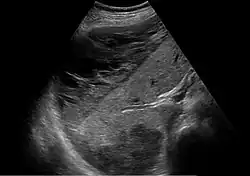

Es besteht das Risiko der schnellen Entwicklung eines Schocksyndroms als Folge von Disseminierter intravasaler Koagulopathie (DIC) (in 4 bis 38 %), akutem Nierenversagen (bis zu 8 %), Lungenödem (bis zu 6 %), Hirnblutung oder der Ruptur eines subkapsulären Leberhämatoms mit intraabdominaler Blutung, sowie einer vorzeitigen Plazentalösung (bis zu 16 %).[3]